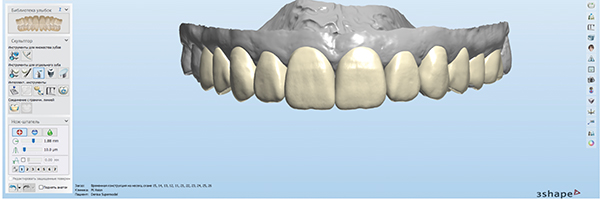

Fig 9. Tooth shapes were selected from a library for the digital wax-up and setup based on the patient’s facial features and esthetic expectations.

Figure 9

Fig 14. The same library of teeth selected and approved by the patient for the original smile design and mock-up was used for the definitive restoration design.

Figure 14

Based on the patient's facial features and esthetic expectations (natural shapes with dominant central incisors), tooth shapes were selected for the digital wax-up and setup (Figure 9). A model was 3D-printed from the digital smile design to fabricate an intraoral direct mock-up with a silicone index and bis-acryl material. This mock-up allows the clinician and the patient to evaluate and verify the smile design (Figure 10). It also serves as an excellent tool to motivate the patient and instill confidence in both the patient and dentist in the planned treatment. Documentation with photographs and videos is essential.

For the definitive restorations design, the CAD designer used the same library of teeth selected for the mock-up, ensuring precise realization of the smile design that the patient had verified and approved (Figure 14). With the software's ability to focus closely on the marginal areas for high precision of fit, microscopic and digital dentistry tools complement each other extremely well. Current milling machines can mill 12 monolithic ceramic units within a few hours with excellent precision. In this case, multi-layer leucite-reinforced feldspathic ceramic blocks were used. Adhering to the patient's individual preferences, the milled restorations were characterized through staining and glazing (Figure 15).